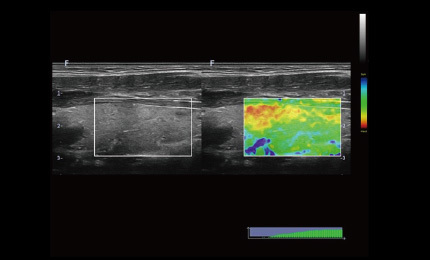

Elastografia w czasie rzeczywistym to nowa nieinwazyjna i bezbolesna technika, która pomaga określić twardość organów oraz innych struktur takich jak piersi czy tarczyca. Obrazowanie elastyczne dostarcza użytkownikom dynamicznych informacji wizualnych i pokazuje sztywność organów, co jest pomocne w bezpośredniej i ilościowej diagnozie oraz leczeniu.